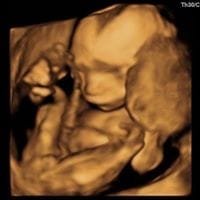

Baja por riesgo en el embarazo siendo canguro